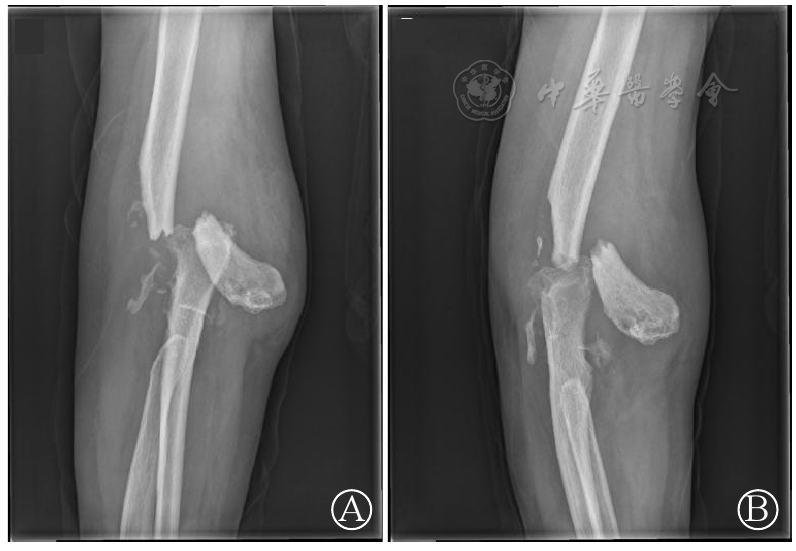

图3 右肘关节全肘关节置换术后正(图A)、侧(图B)位片:右侧人工肘关节对应关系可,位置正常、稳定

图4 右肘关节正(图A)侧(图B)位片:右侧肘关节置换术后,右侧肱骨下端骨折,断端明显分离移位,关节周围软组织内可见游离骨片影,软组织肿胀

图5 右肘关节假体周围骨折术后正(图A)、侧(图B)位片:右肱骨骨折断端对位对线尚可,内固定稳定,周围软组织内可见小游离骨折碎片,右侧人工肘关节位置良好